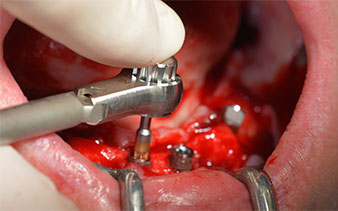

After removal of the residual dentition in the mandible, the alveolar crest was exposed from 37 to 47.

The mental foramen was first identified as a limiting anatomical structure and then the cortical bone of the crest was smoothed with the straight handpiece and a large rose-head bur (Fig. 4).